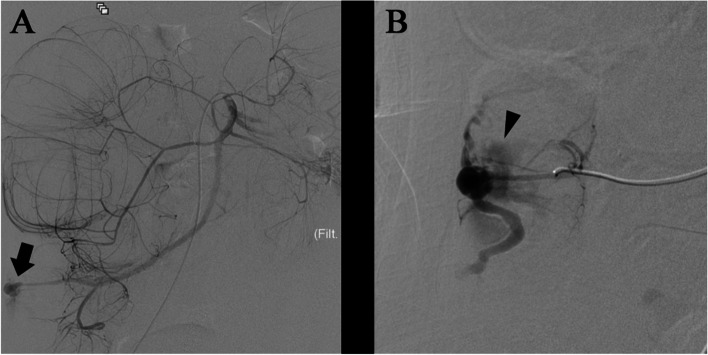

Coils were placed as scaffolds to decrease the blood flow. An additional 33% N-butyl cyanoacrylate and iodized oil mixture were carefully administered to fill the coils. Localized blood flow control and hemodynamic stability were achieved via embolization. Postoperative contrast leakage was not observed (Fig. 4).

Fig. 4.

Superior mesenteric artery angiography after embolization. Embolization of the distal ileocolic artery was successfully performed using coils and N-butyl cyanoacrylate, and no contrast leakage was observed